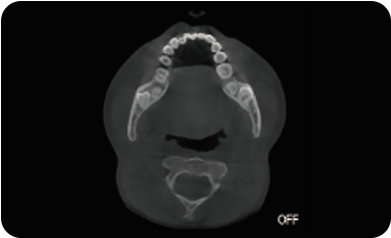

局部超清显示、 移动视野摄片

真人正侧位投影,实现CT成像区域无极可调

可根据临床需求任意调整成像区域大小实现局部超清三维显示

临床样片